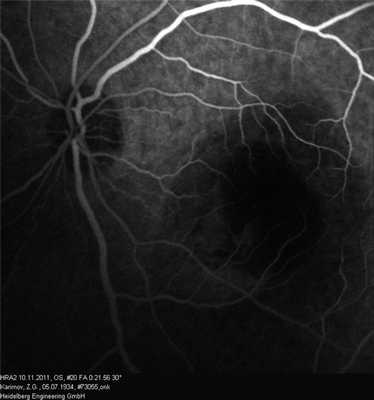

Офтальмоскопия: OD — в центральной зоне глазного дна единичные мелкие просовидные очажки округлой формы. На периферии очаговой патологии не выявлено (рис. 1, а). Рисунок 1. Офтальмоскопия друз (а) и проминирующего очага (б). Здесь и на рис. 4, а, б: желтой стрелкой указана зона глазного дна, на уровне которой проведен томографический срез методом СОКТ.

OS — в макулярной зоне в 1,5 pupilla diametr (PD) от диска зрительного нерва по меридианам с 14 до 16 ч определялся проминирующий желтый беспигментный очаг с гладкой поверхностью, нечеткими неровными границами, размером 2×2 PD (см. рис. 1, б).

Флюоресцентная ангиография: OD в венозную фазу — несколько мелких гиперфлюоресцирующих округлых фокусов (друзы).

OS — в макулярной зоне выраженная гипофлюоресценция очага с четкими границами, окруженная обширной зоной гиперфлюоресценции (отслойка нейроэпителия — НЭ). В парамакулярных зонах — очаги гипофлюоресценции (микроотслойки ретинального пигментного эпителия — РПЭ) и множественные мелкие гиперфлюоресцирующие округлые очаги (сливные друзы) (рис. 2). Рисунок 2. Флюоресцентная ангиография поздней стадии возрастной макулярной дегенерации, проявляющейся проминирующим очагом (объяснения в тексте).